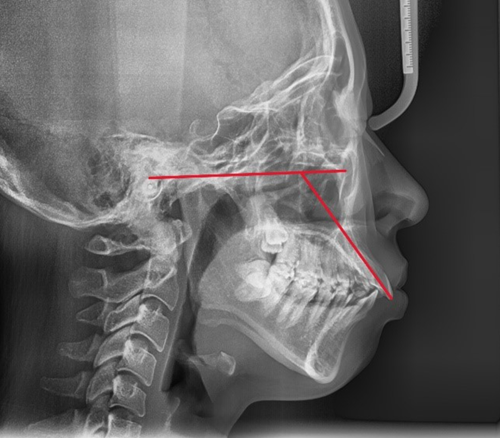

돌출입인지 아닌지를 판단하는 기준은 여러 가지가 있으나, 그 중에서 가장 간단한 방법 중 하나는 측면에서 코 끝과 턱 끝을 일직선으로 연결했을 때 입술의 위치를 평가하는 것입니다.

입술이 그 라인보다 앞쪽에 있다면 돌출입으로 판단할 수 있습니다.

돌출입의 유형은 크게 3가지로 나눌 수 있습니다.

첫째, 골격성(턱뼈 자체가 튀어나온) 돌출

둘째, 치아 각도가 뻐드러진 경우

셋째, 위 두 가지가 복합적으로 나타나는 경우

치성 돌출